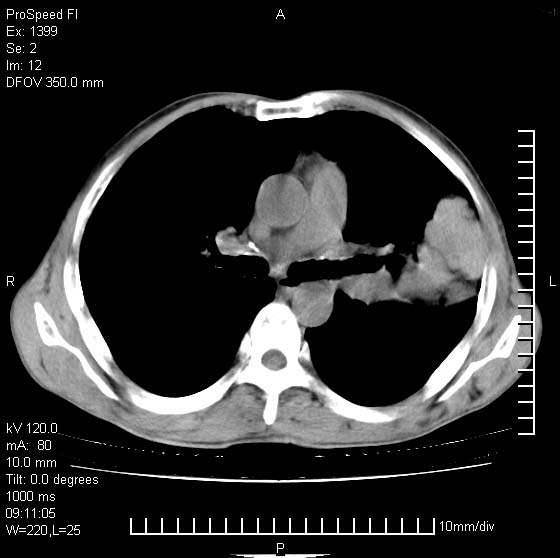

以下是引用卜一在2007-1-19 9:55:00的发言:[br]左肺沿胸膜下巨大肿块影,边缘呈分叶征,纵隔内见肿大淋巴结,右肺内另见一不规则结节影 .考虑:左肺周围性肺癌伴纵隔 右肺内转移.